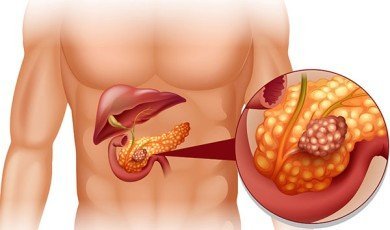

Pancreatic Diseases Overview

With the right treatment and lifestyle c...